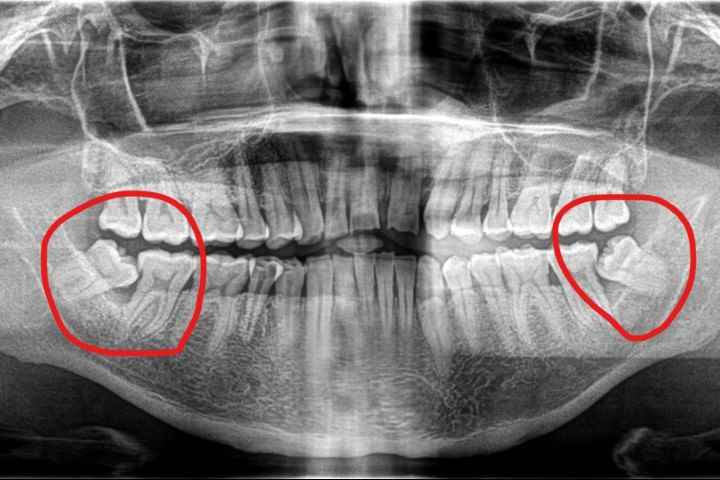

If you are missing wisdom teeth, there is no need to reconstruct them because they have no practical function and do not affect the appearance. But what often happens is that when the wisdom tooth decays, it also harms the adjacent second molar. When the patient comes to the clinic, both teeth are decayed and even have to be extracted at the same time. At this time, because the second molar is also not If it is destroyed, it must be rebuilt.

Therefore, you will often hear dentists remind you: "Before the wisdom teeth have any problems, you should evaluate whether they need to be removed!" There is a reason why doctors make such recommendations.